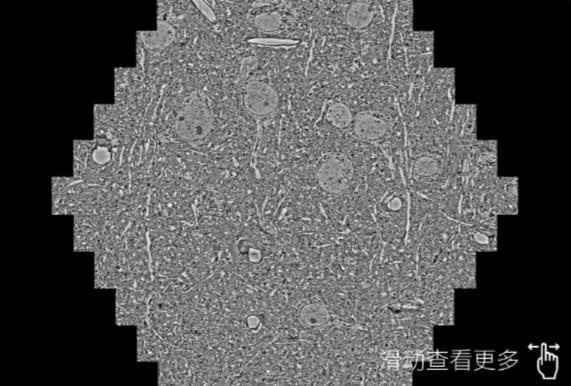

鼠脑切片。左图使用莱芜蔡司莱芜扫描电镜MultiSEM706对165μmx143pm面积区域成像,耗时仅需1.5秒。右图为鼠脑切片中30μm区域放大效果。样品由芝加哥大学B.Kasthuri提供。